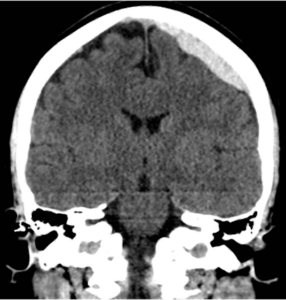

急性硬膜下血腫とは強い頭部外傷によって脳と硬膜の間の血管が損傷し、脳の表面に硬い血液が溜まって脳を圧迫する状態です。受傷直後から数時間以内に出血が進行しやすく意識障害や運動麻痺などの神経症状をきたすことがあります。血腫が大きくなると生命の危険が生じるため手術が必要になることが多いです。急性硬膜下血腫は非常に重篤な頭部外傷であり早期診断と治療が予後を左右します。